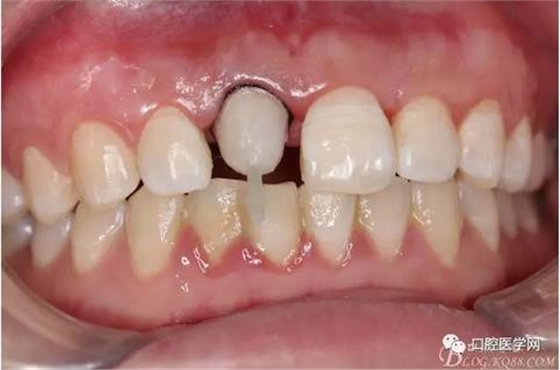

術(shù)前口內(nèi)照,11殘根,唇側(cè)牙齦紅腫,肩臺(tái)在齦下2毫米,舌側(cè)正常.21有被動(dòng)萌出,長(zhǎng)寬比例不協(xié)調(diào)??谇恍l(wèi)生一般,有菌斑。

術(shù)前原有牙冠復(fù)位,牙齦紅腫。